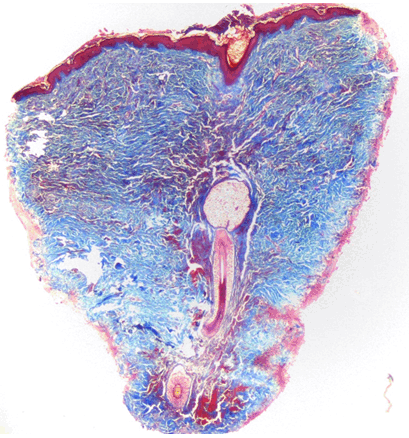

An 18-year-old female with history of delayed milestones, low IQ, and typical Mongolian facies (Figure 1) (typical slant of forehead, and macroglossia) presented to our outpatient department with abrupt onset of asymptomatic skin colored nodules within a period of one month on upper back. The patient did not report any previous history of chicken pox/ trauma at the involved site. Her family history was unremarkable. A review of the various organ systems (cardiovascular, respiratory, gastrointestinal tract, central nervous system) was within normal limits. Examination revealed multiple, discrete, firm, non-tender, skin colored nodules measuring 0.5 to 2 cm in diameter with no scaling or exudation on the surface. The lesions were present predominantly on upper 2/3 of back and on thorough cutaneous examination similar lesions were present on the mons pubis, which as per patient developed 6 months back (Figure 2) and (Figure 3). We kept the differentials of eruptive xanthoma, steatocystoma multiplex and eruptive collagenoma. There was no evidence of hypopigmented macules on wood's lamp examination or skin lesions suggestive of tuberous sclerosis. There was no significant past medical or surgical history. The hematological and biochemical investigations including complete blood count, renal, liver function tests, urine analysis, lipid profile, electrocardiogram, abdominal ultrasound and chest roentgenogram were within normal limits. Skeletal survey did not demonstrate any evidence of osteopoikilosis. A skin biopsy obtained from the lesion on upper back and mons pubis showed focal acanthotic epidermis and significantly increased density of collagen bundles in the deep reticular dermis (Figure 4). Masson's trichrome stain confirmed the presence of dense collagen bundles with decreased elastic fibers (Figure 5). Thus a diagnosis of sporadic eruptive collagenoma with Down syndrome was made.

Figure 5: Masson trichome stain: Increased collagen bundles in dermis (blue).